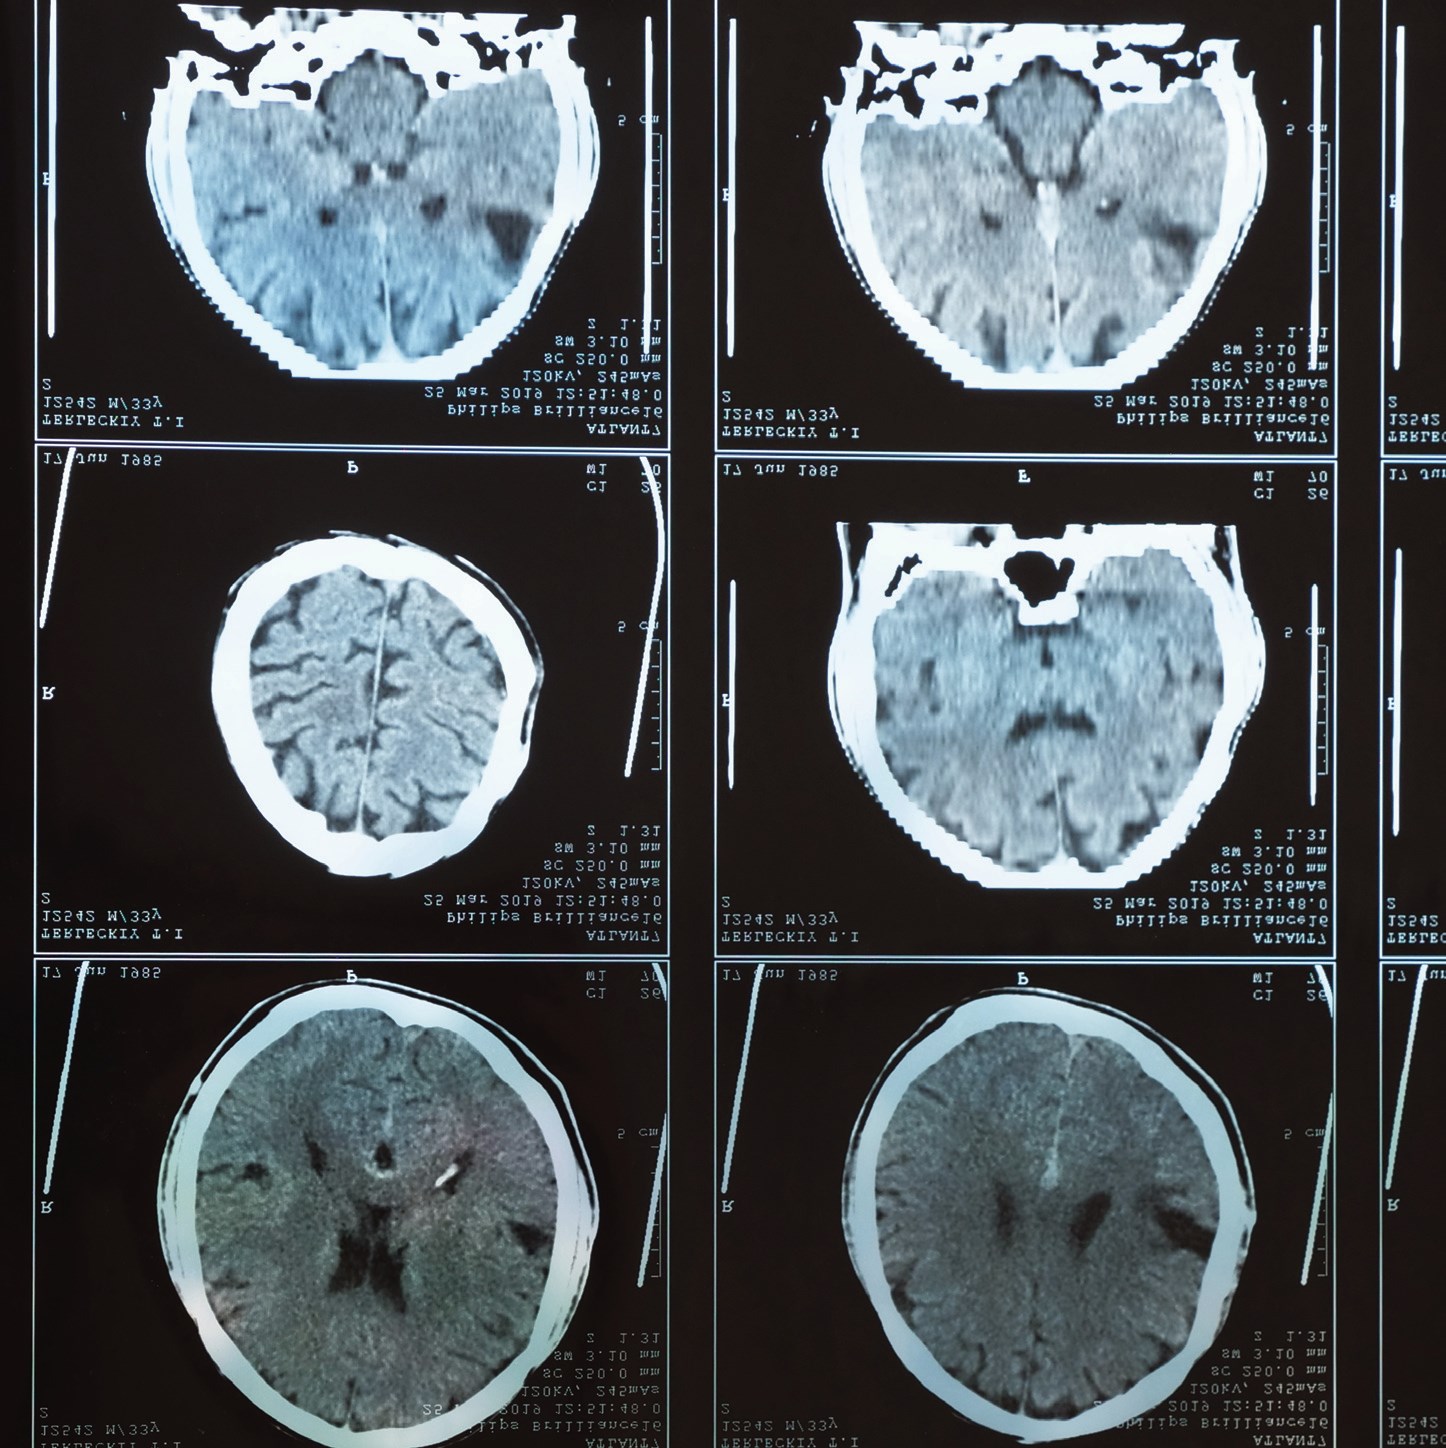

Alzheimer’s is the most common form of dementia, a progressive, degenerative brain disease that impairs memory, thinking and behavior.